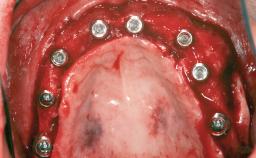

Ridge Preservation and Implant Placement for a Fixed Dental Prosthesis After a Car Accident

It is well known to clinicians that any removal of teeth will, over time, cause the dimensions of the alveolar ridge to be reduced by resorption of the bundle bone and by changes related to external modeling. This development is particularly evident in the crestal region with its thin buccal bone that consists of bundle bone almost entirely. The facial bone will rapidly resorb as blood supply from the periodontal ligament gets disrupted (Araújo and Lindhe 2005). There is no reason why traumatic tooth loss should not have the same consequences. It takes more than achieving implant osseointegration for a treatment outcome to be considered successful. No deficiency of bone or soft tissue is acceptable when an ideal esthetic outcome is the goal. Several articles (Sanz and coworkers 2011; Vignoletti and coworkers 2011) have reported on techniques of improving the alveolar ridge for implant treatment, notably focusing on protecting tissues from resorption.

# of Implants 4

Type of Implants One-Piece|Reduced-Diameter